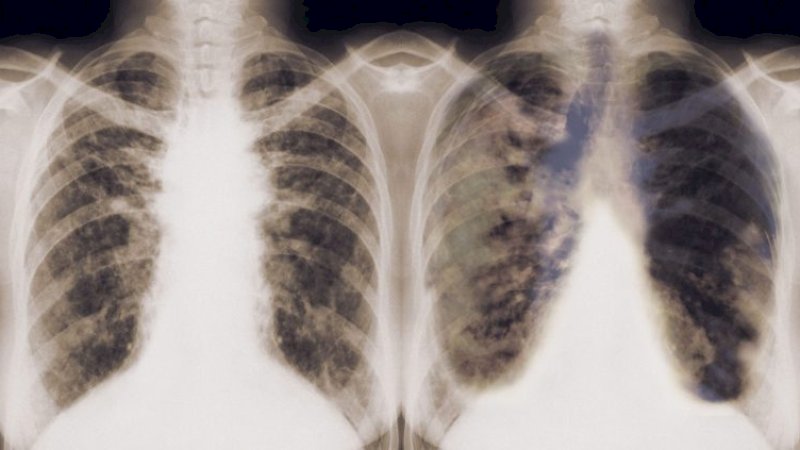

Perusahaan ini bermitra dengan para profesional medis untuk mengembangkan sebuah algoritma yang dapat mendeteksi kanker paru-paru.

Dalam sebuah laporan yang diterbitkan dalam jurnal Nature Medicine, peneliti mengungkapkan bahwa AI bahkan lebih akurat daripada ahli radiologi terlatih dalam mengetahui tanda-tanda kanker dalam pemindaian medis.

Dalam hal ini, otak komputer dilatih menggunakan pemindaian dari skrining kanker paru-paru masa lalu. Kemudian itu ditugaskan untuk menilai lebih dari 6.700 scan skrining kanker untuk melihat seberapa akurat itu dalam mendeteksi kanker yang sudah diketahui oleh para dokter.

Rupanya, hasil menunjukkan bahwa algoritma itu mencapai akurasi 94,4%.